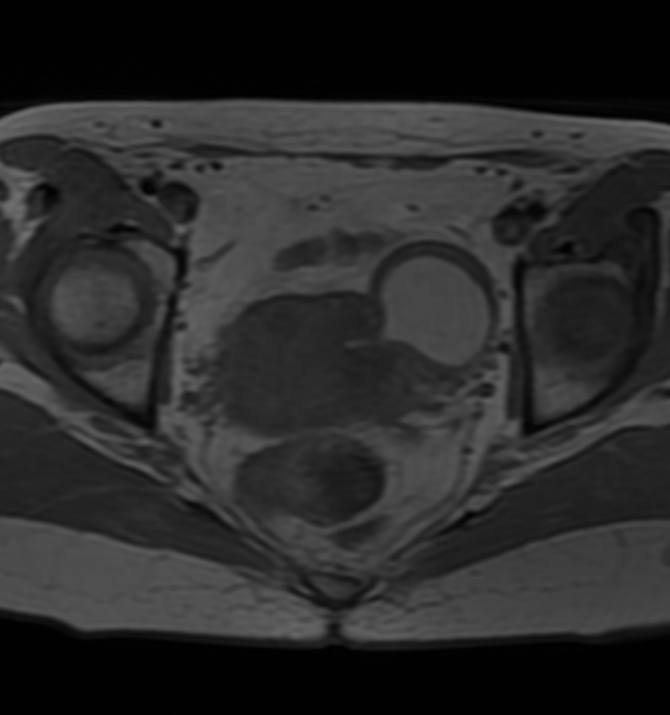

Дивертикул матки у женщины 45 лет.

Дивертикул матки - это редкий врожденный порок развития, вызванный аномальным слиянием мюллеровых протоков.

Диагноз дивертикула матки затруднен, и его часто неправильно диагностируют как другую аномалию Мюллерова протока (например, кровь в рудиментарном роге матки), миому матки с дегенерацией, эндометриому или геморрагическую кисту яичника.

Встречается так редко, что я, вот, первый раз сам увидел, и то, спасибо коллеге из Алма-Аты.

Спасибо, Диас!